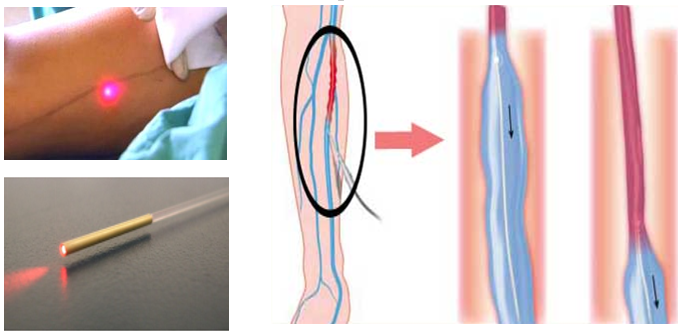

4、介入治疗:KTS的介入治疗主要包括病灶中外侧浅静脉、静脉畸形、淋巴管畸形的硬化治疗。静脉畸形介入治疗的原则是局部或经导管注入血管硬化剂类药物,其作用机制是使其内皮变性坏死,继而血栓形成,闭塞畸形血管腔;是目前KT患肢最主要的治疗方式。

目前,KT综合征中下肢血管内消融治疗主要针对肢体性或部分特殊性躯体KT综合征患者,其原理是通过多种热消融器械(激光/微波/射频等)以及血管内植入物来闭合异常静脉(边缘静脉/胚胎静脉/持续性坐骨静脉)来改善患者病变部位血液循环,从而减少肢体肥大/出血/疼痛/无力等症状,这个术式随着血管腔内治疗的兴起逐渐成为KT患者治疗的主流方式,具有微创、恢复快、不影响活动、疗效确切等优点,对患者年龄没有特殊要求。